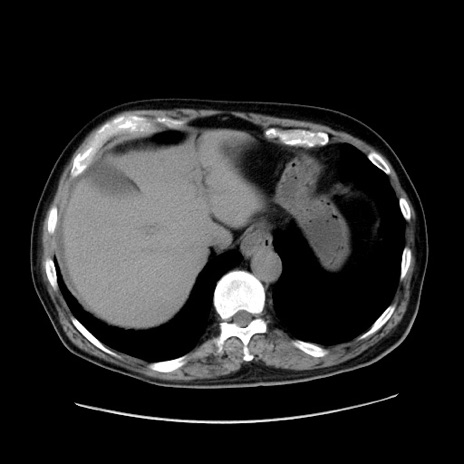

症例30(横断像)

【症例】80歳代男性

【主訴】臍周囲痛

【現病歴】約6時間前から臍下部痛が出現。次第に腹部膨隆・背部痛も生じてきたため来院。背部痛の場所は変化しない。

【身体所見】意識清明、BT 36.3℃、BP  131/87mmHg、P 87bpm、SpO2 100%(RA)、臍周囲自発痛・圧痛あり、反跳痛なし、自発痛部位に一致して板状硬あり、腹部膨隆、腸雑音減弱、CVA tenderness両側陰性。

【データ】WBC 19600、CRP 0.33